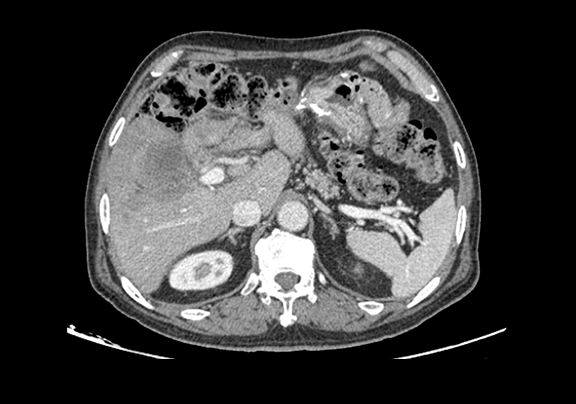

下腹部增强CT示:肝右前叶胆管细胞癌并胆管扩张可能性大。

将0.625mm双源薄层CT资料的静脉期和动脉期Dicom格式文件导入海信CAS系统。

通过调节窗宽窗位调整CT序号,对肿瘤,肝实质,胆囊,下腔静脉,肿瘤,肝动脉、门静脉及肝静脉等进行三维重建;系统自动计算肿瘤体积和肝脏体积。(图2—截图1---后链接截图2)

模拟手术操作,自动计算切除肿瘤体积。肝脏体积为1324ml,肿瘤体积为286.1ml,肿瘤体积为肝脏体积的21.6%,通过比对70-80岁正常肝脏体积为1118.08±190.14ml,通过术前模拟手术,精准判断切除后剩余肝脏体积能耐受,避免肝衰竭发生。术前手术方案的规划。

术前CT检查:

动脉期

静脉期

平衡期